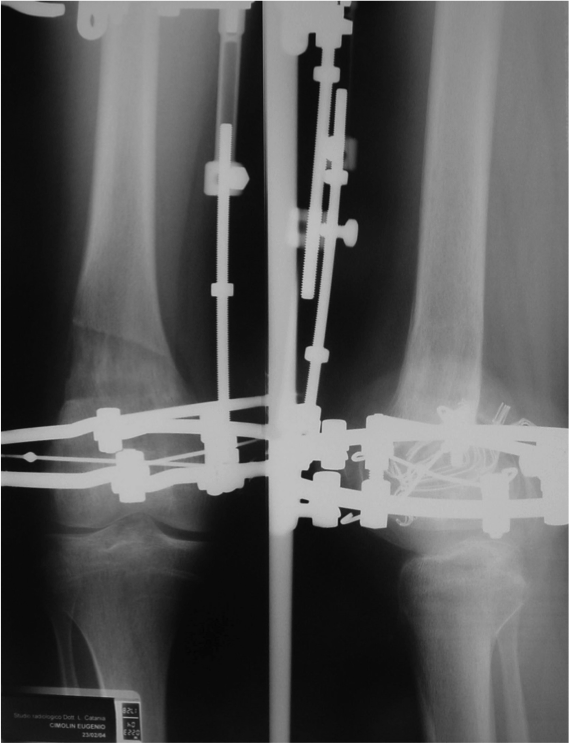

Maschio 13 anni. Esiti di frattura epifiolisi di condilo femorale esterno in eta di 10 anni.

Deformita in valgo del femore e accorciamento di 2,5 cm.

Inizio di correzione delle deformità

Inizio di allungamento